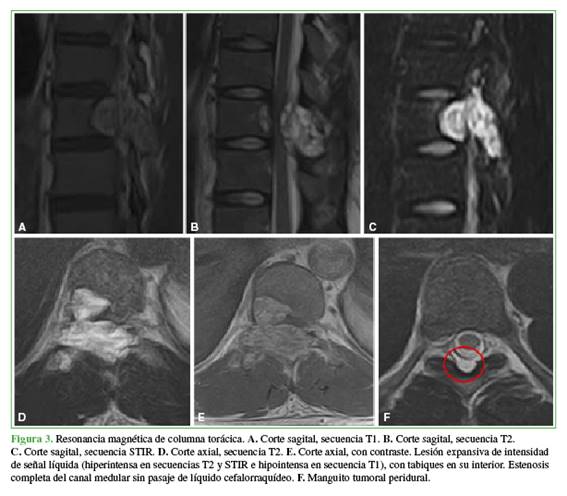

Al ingreso se solicitaron estudios por imágenes. La radiografía evidenció el signo del “guiño del búho” a nivel de la décima vértebra torácica (T10) (Figura 1).

En la resonancia magnética de columna torácica, se identificó la misma lesión expansiva, con contenido líquido y con extensión al canal torácico, lo que generaba compresión medular y estenosis del canal, sin permitir el pasaje de líquido cefalorraquídeo (Figura 3).